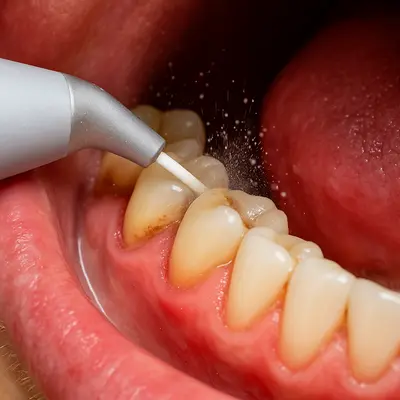

انجام جرمگیری دورهای و معاینهٔ منظم توسط دندانپزشک نیز به شناسایی زودهنگام پوسیدگیهای سطحی کمک میکند.

در قدم اول، باید با رعایت دقیق بهداشت دهان و دندان جلوی پیشرفت آسیب را بگیرید. مسواکزدن دو بار در روز، استفاده از نخ دندان بعد از غذا، و انتخاب خمیردندان ضدحساسیت، میتواند درد را کاهش دهد و از تحریک بیشتر عصب جلوگیری کند. انجام جرمگیری دورهای و مراجعهٔ منظم به دندانپزشک نیز از تجمع باکتریها و پوسیدگیهای پنهان جلوگیری میکند.